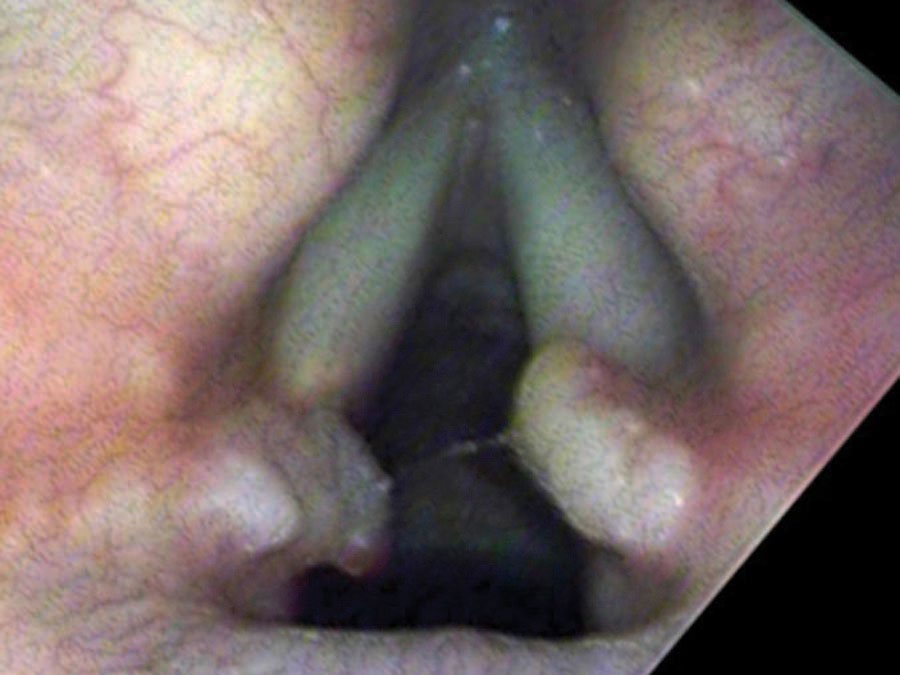

The Life Cycle of a Granuloma

From injury to resolution, granulomas follow a predictable evolution. New ulcers from overuse initially split into two parts where the opposite vocal process rests in a groove during closure. Gradually, granulation tissue heaps up around the traumatized point, forming a mass. In the middle of their lifespan granulomas become yellow or red and round. Later the mass tends to harden, become white and spherical, and the base narrows to a stalk. At this stage the granuloma may flip up out of the way during phonation and no longer impairs closure — so vocal capabilities testing can return to normal even while the granuloma is still present.

In Sam’s case, the strategy combined two injections delivered in the office: a steroid (triamcinolone) injected directly into the granuloma to reduce its size, and botulinum toxin injected into the LCA muscle to weaken closure of the vocal cords — reducing the impact of the vocal processes against each other. When he returned two months later, the granuloma had shrunk rather than being coughed out as often happens.